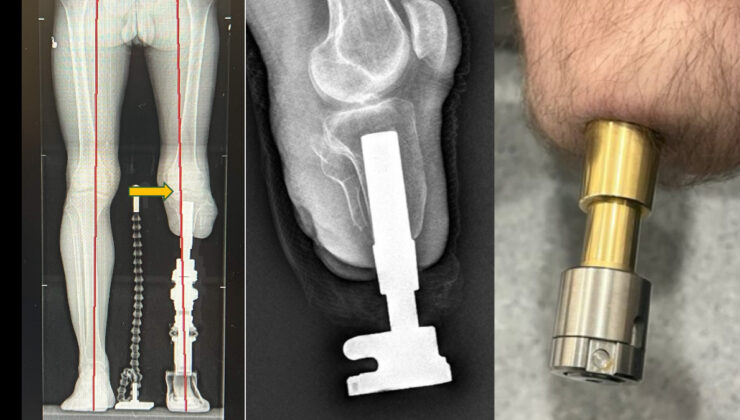

Klasik soket protezlerin yol açtığı ağrı, yara ve yürüme zorluklarına bir alternatif sunan osseointegrasyon prosedürü, amputasyon hastalarına umut veriyor.

Kemiğe yerleştirilen implantlarla daha doğal ve konforlu bir yürüyüş sunan bu prosedür Türkiye’de de uygulanıyor.

Bu metotta, kemiğe yerleştirilen implant sayesinde yük direkt kemiğe aktarıldığından, çok daha doğal ve konforlu bir yürüyüş mümkün oluyor.

Osseointegrasyon protezlerinin yapıldığı uzuvlar hakkında da bilgi veren Prof. Dr. Kara, yöntemin uyluk, kaval kemiği, dizüstü ve dizaltı üzere bölgelerin yanı sıra üst kol amputasyonlarında da muvaffakiyetle uygulandığını aktardı.